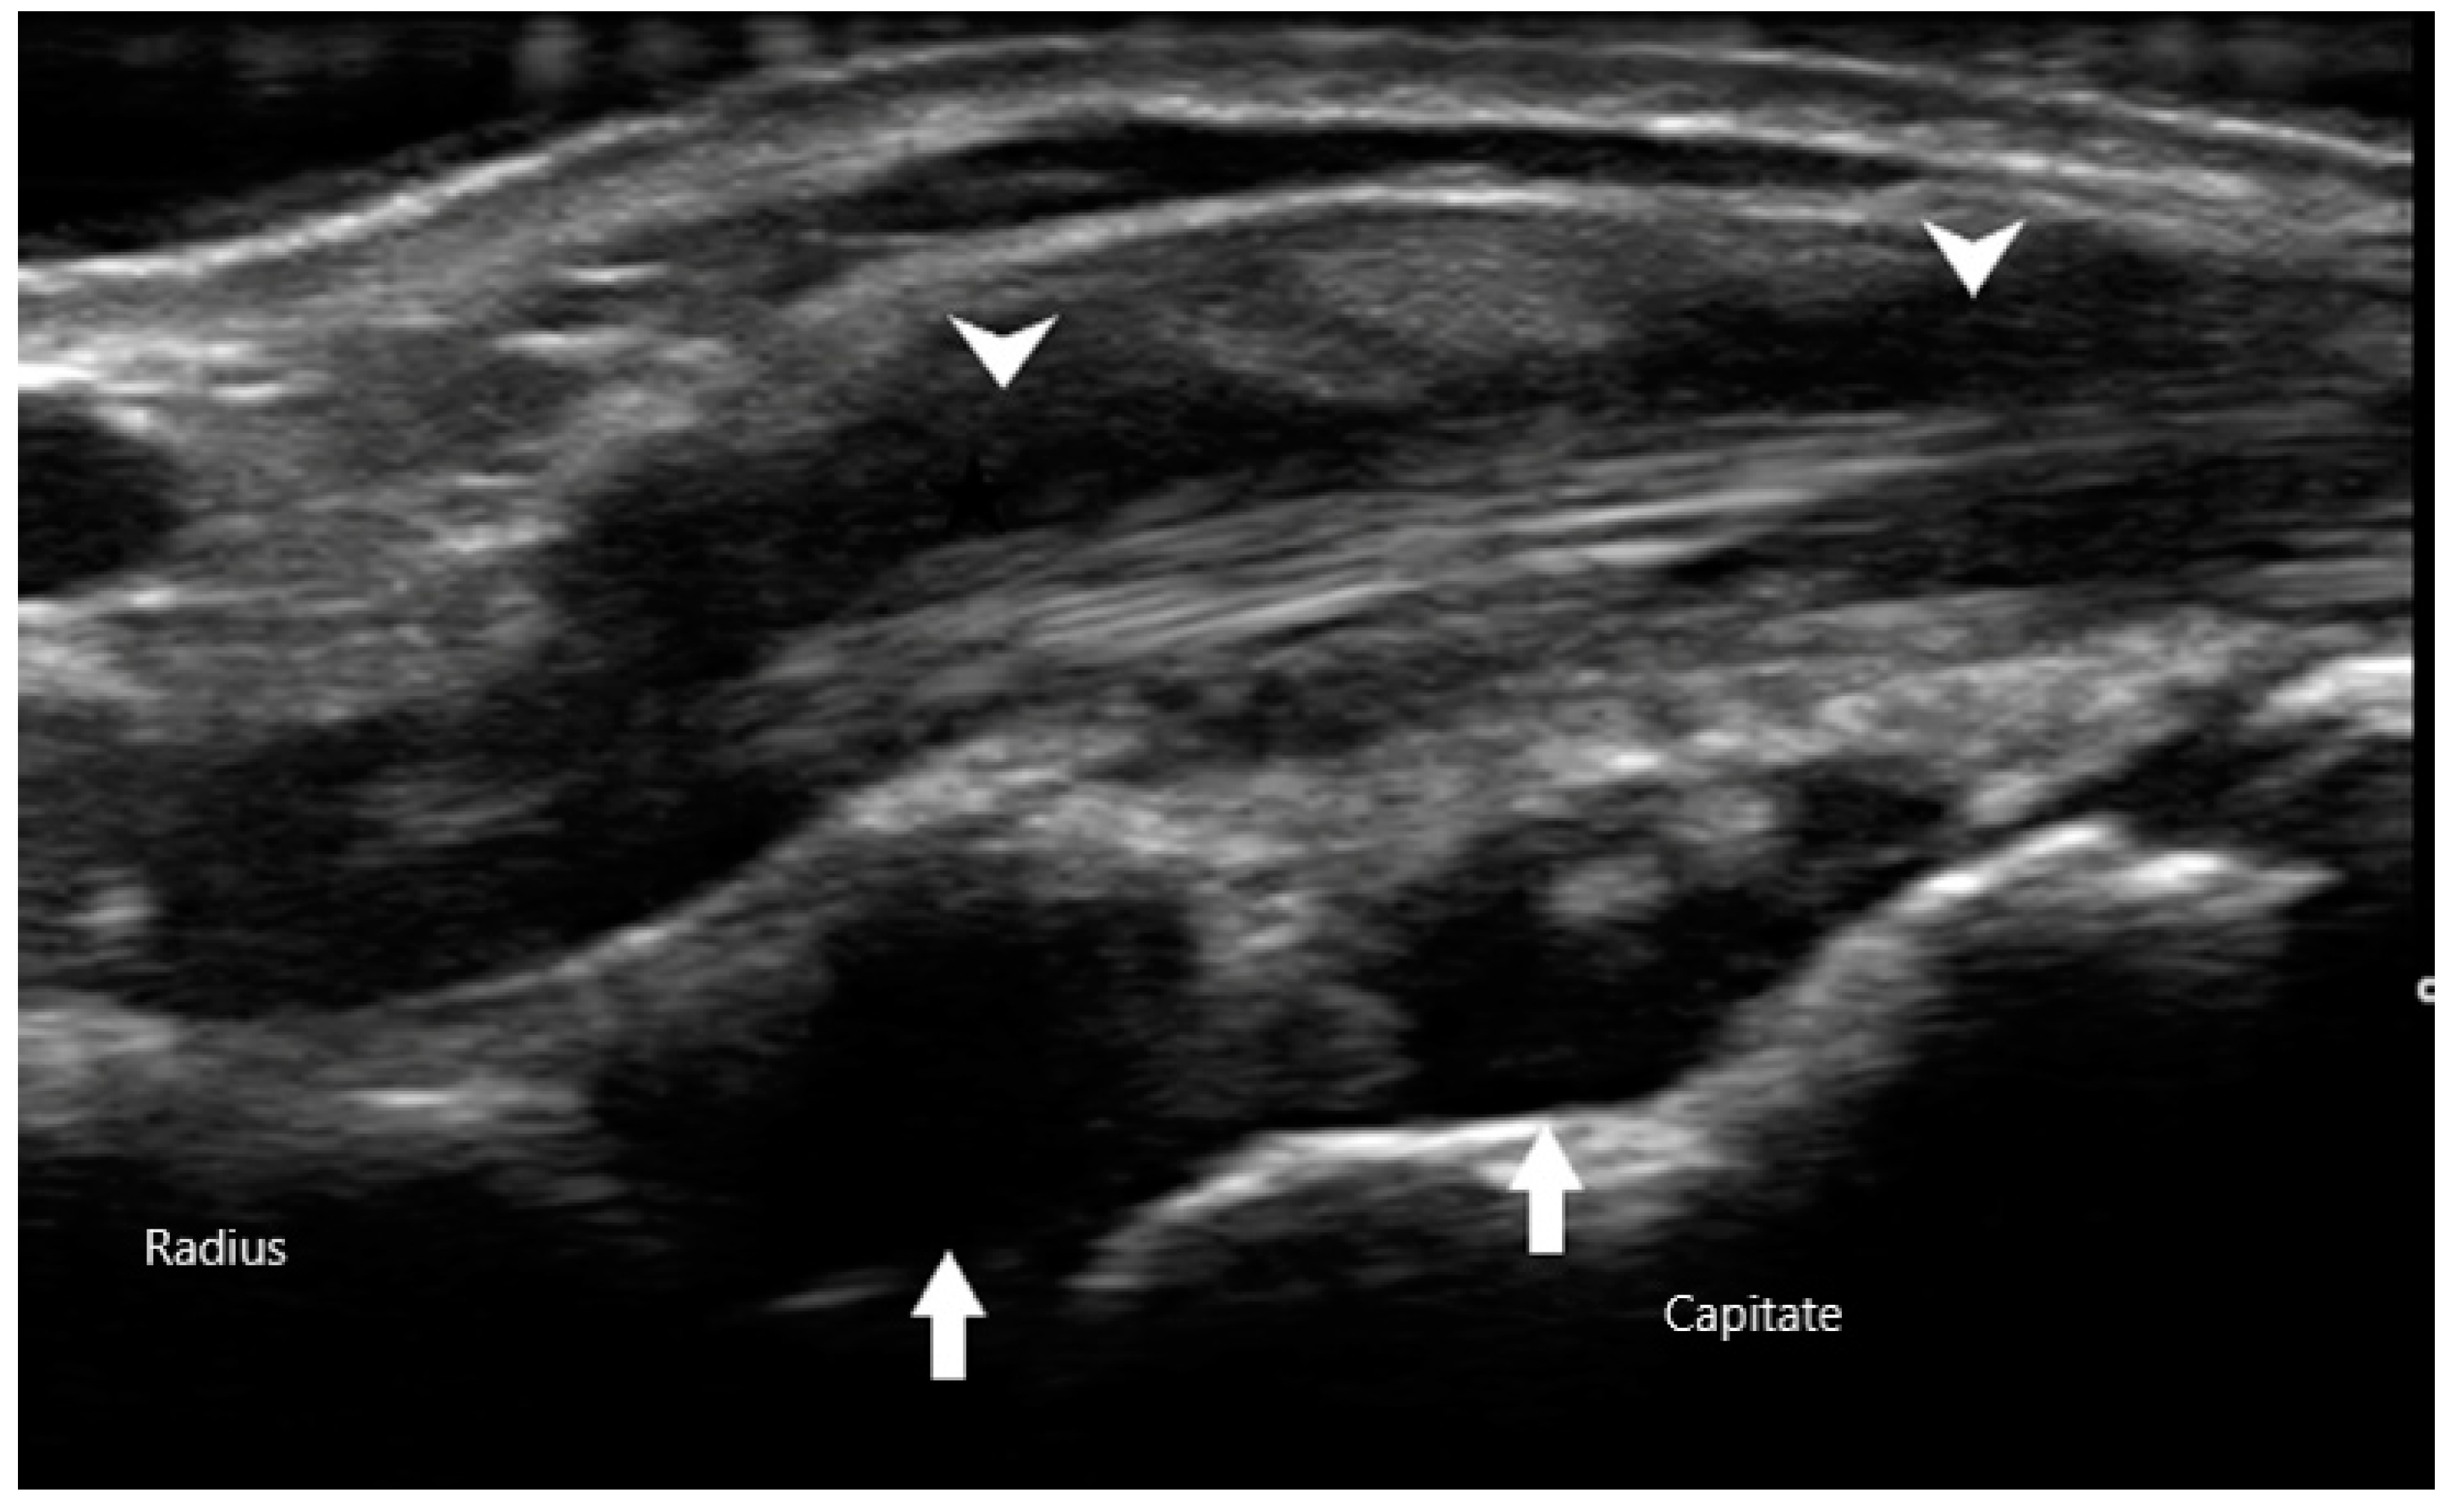

The Outcomes Measures in Rheumatology (OMERACT) group has established a consensus-based system to define and grade synovitis identified by greyscale and power Doppler [19]. Synovial hypertrophy is visualized as abnormal hypoechoic material in intra-articular tissue that is non-displaceable and non-compressible (Figure 2). In order to distinguish it from an effusion, sonographers can apply pressure on the transducer in order to evaluate for compressibility. It is graded on a scale of 0 to 3. Grade 1 is defined as minimal synovial thickening without protrusion over the adjacent bone. Grade 2 is more extensive synovial thickening with bulging over the bone. Grade 3 describes extensive thickening with extension beyond the joint. Angiogenesis is another hallmark of synovitis, and this hypervascularity can often be detected by increased power Doppler signal, which can also be graded from 0 to 3 [20]. Grade 0 refers to lack of Doppler activity. Grade 1 is mild activity. Grade 2 and 3 are defined as Doppler signals covering <50% and >50% of the joint area respectively. Tenosynovitis is characterized by hypoechoic material or fluid within tendon sheath (Figure 3).

Figure 3. Synovial hypertrophy (arrows) of radiocarpal joint with tenosynovitis (arrowheads) of extensor tendon.